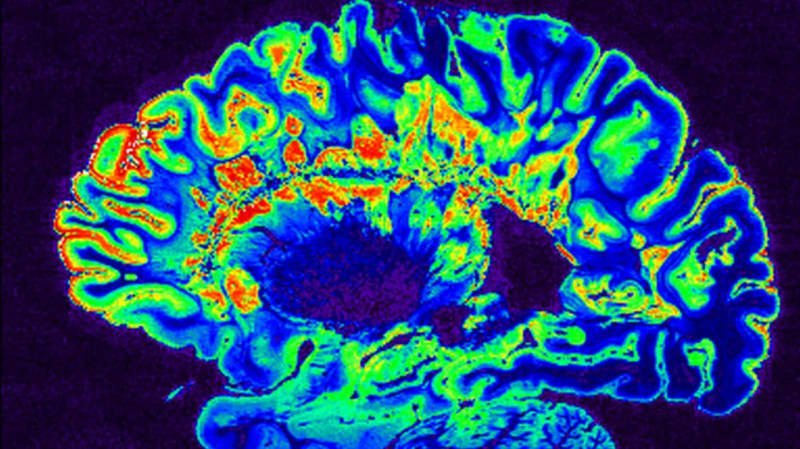

Alzheimerova choroba je neurodegenerativní onemocnění, při kterém postupně odumírají nervové buňky (neurony) v určitých částech mozku, což vede k postupné ztrátě paměti, myšlení a schopnosti se o sebe postarat.

Čeští vědci vedení Milanem Němým z ČVUT využívají umělou inteligenci k odhalování drobných problémů v mozku, které mohou předcházet rozvoji duševních onemocnění, jako je Alzheimerova choroba. Pomocí moderních metod magnetické rezonance (MRI) se zaměřují na zachycení jemných změn v mozkových strukturách a jejich propojení, které nelze snadno vidět. #UměláInteligence #VýzkumMozku #AlzheimerovaChoroba

Najít v mozku drobné problémy, které mohou jednou přerůst třeba v Alzheimerovu chorobu, to je cílem výzkumu Milana Němého z ČVUT.